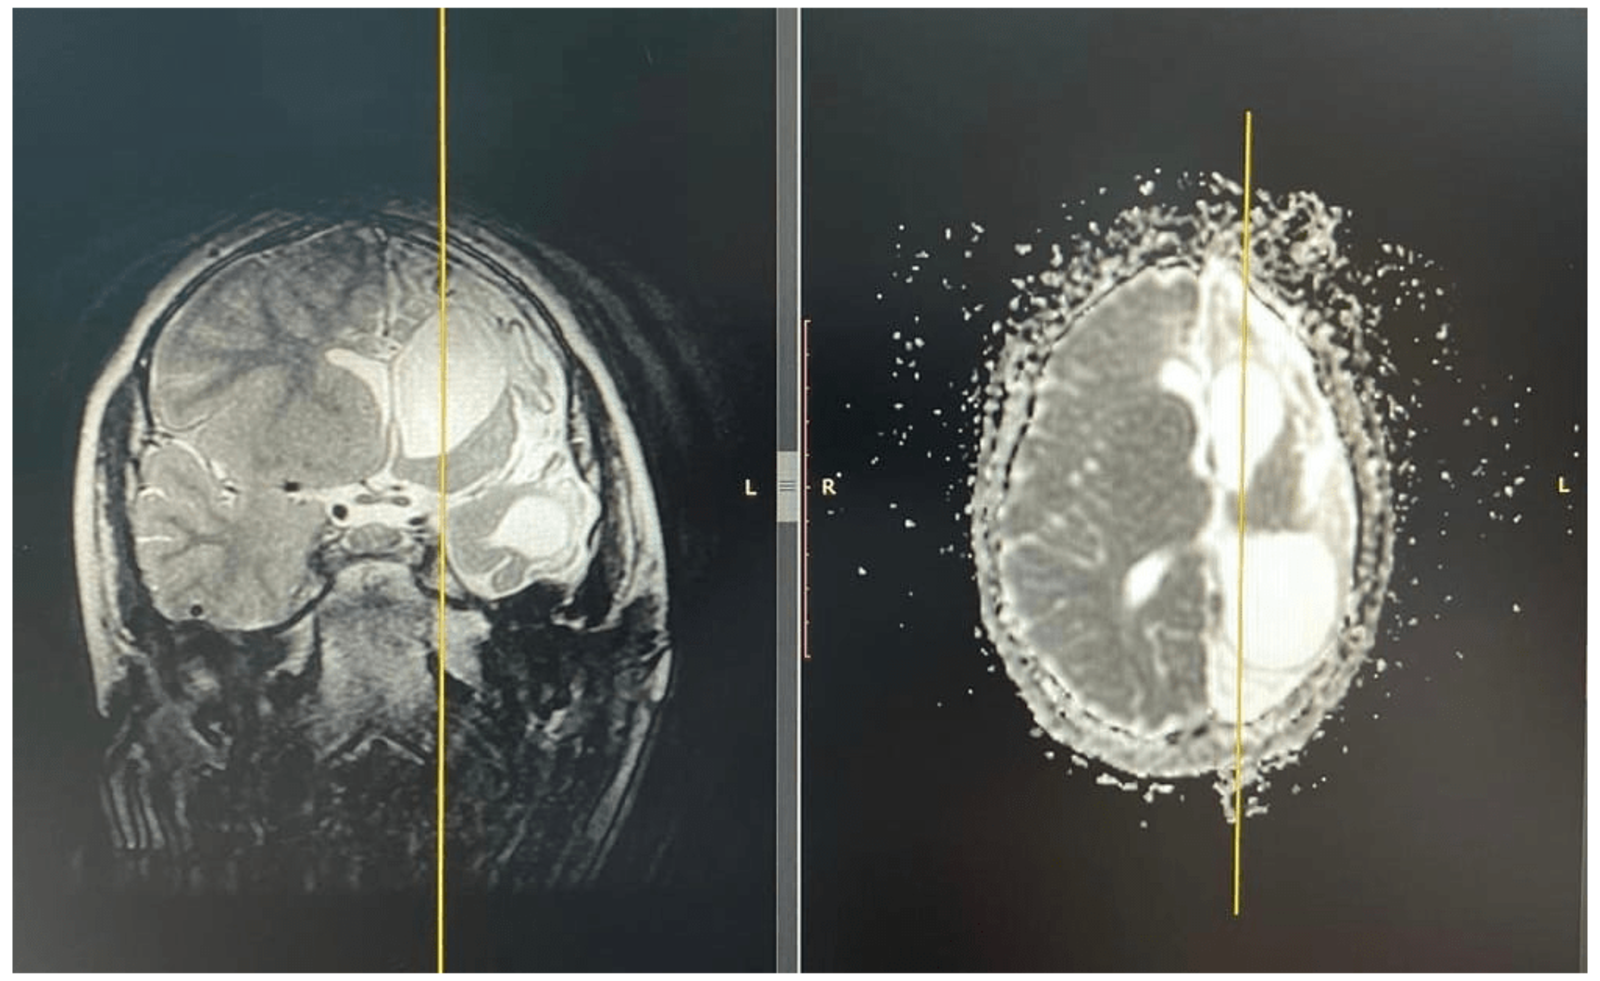

Медики республиканской детской клинической больницы в Уфе провели уникальную операцию пятилетнему мальчику. Ребенок болен редкой формой эпилепсии, сообщает региональный минздрав. Эпилептические припадки случались у него до ста раз в сутки.

Операция состоялась в первый день осени, по-научному она называется гемисферэктомия и проводится в единичных больницах страны.

Фото предоставлено пресс-службой минздрава РБ